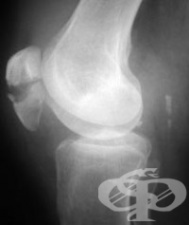

АКЦЕНТИ ОТ РУБРИКА РЕНТГЕНОВИ ИЗСЛЕДВАНИЯ (БЕЗ И С КОНТРАСТНО ВЕЩЕСТВО)

АКТУАЛНО ОТ РУБРИКА РЕНТГЕНОВИ ИЗСЛЕДВАНИЯ (БЕЗ И С КОНТРАСТНО ВЕЩЕСТВО)